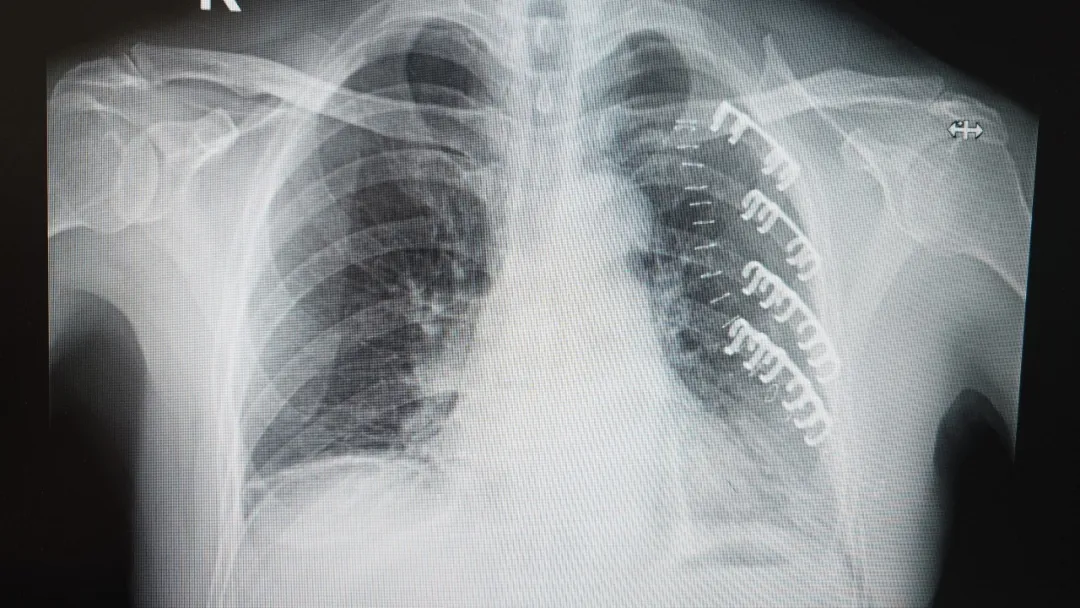

患者術(shù)后CT影像

術(shù)后僅僅2小時,李大爺就能在指導(dǎo)下小口喝下流食。更令人難以置信的是,手術(shù)當(dāng)晚,在醫(yī)護(hù)人員專業(yè)指導(dǎo)和嚴(yán)密監(jiān)護(hù)下,李大爺竟然可以小心翼翼地坐起,并在攙扶下嘗試著地站立活動!“哎呀!真是沒想到!胸口不那么疼了,這么快就能動,感覺像換了個人似的!”病床上的李大爺難掩激動,向?qū)O振教授連連道謝。

孫振教授帶領(lǐng)胸外科精干團(tuán)隊,迅速進(jìn)行周密術(shù)前討論。果斷為李大爺實施了“肋骨骨折經(jīng)皮切開接骨板內(nèi)固定術(shù)+胸廓成形術(shù)”。術(shù)中采用先進(jìn)的記憶合金金屬骨板,能完美貼合肋骨弧度,像精密的“環(huán)抱器”一樣,牢牢固定住骨折部位,為脆弱的胸腔構(gòu)建起堅固的支撐。整個手術(shù)過程僅耗時50分鐘,高效精準(zhǔn)!

孫振教授介紹,“對于多發(fā)移位性肋骨骨折,傳統(tǒng)保守治療需長期臥床,易引發(fā)并發(fā)癥。而記憶合金內(nèi)固定術(shù)能立即穩(wěn)定胸廓,且肋骨骨板生物相容性佳,無需取出,避免了二次創(chuàng)傷,顯著提高老年患者的生活質(zhì)量。該技術(shù)適用于多發(fā)、錯位明顯的肋骨骨折,能有效防止骨折斷端刺破肺組織?!?/span>